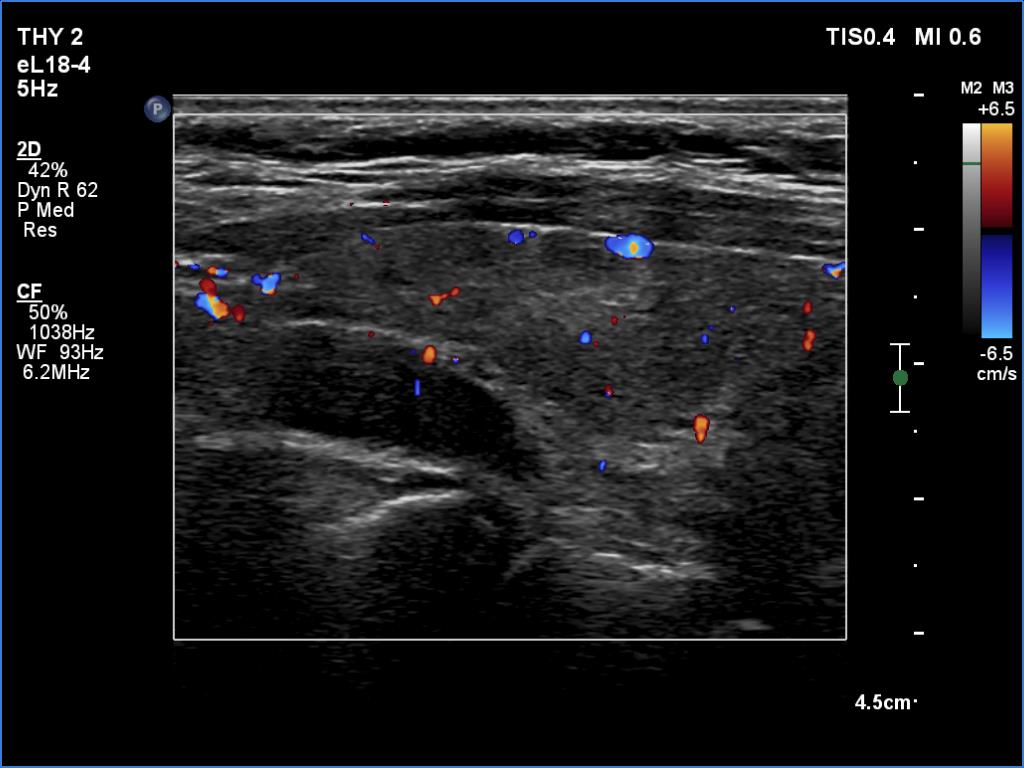

Clinical data: A 61-year-old woman was referred for preoperative localization of a parathyroid adenoma. The patient has been treated for hypothyroidism for seven years. Recently, hyperparathyroidism was diagnosed on evaluation of osteoporosis. MIBI scintigraphy disclosed increased uptake according to one of the left parathyroids.

Ultrasonography. The thyroid was moderately hypoechoic. There were two discrete lesions in the right lobe while a hypoechoic mass was found dorsal to the middle third of the left lobe.